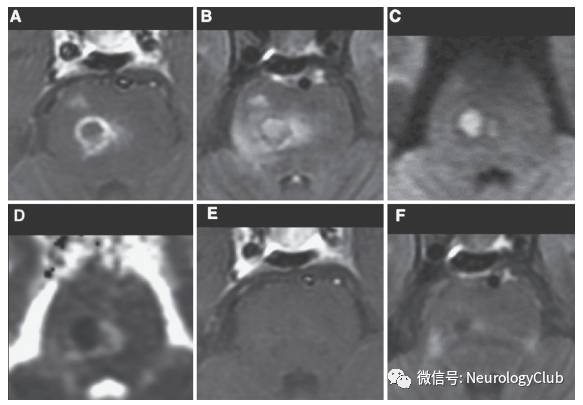

神经白塞病包括实质型和非实质型。实质型神经白塞病约占70-80%,病灶以脑干(脑桥、中脑)常见,也可延伸累及间脑、基底节区。累及大脑半球时,常为多发的小白质病变,也可表现为孤立性类瘤样病灶。脊髓受累时可见单发或多发的不同长度的炎性病变,常位于颈胸髓。也可有脑膜脑炎,表现为脑膜强化。急性期病灶在T1WI上呈等-低信号,增强通常为片状强化,也可出现环形强化,T2WI和FLAIR上为高信号,DWI上高信号,相应ADC值降低。部分病灶中心或周围可见出血。累及脊髓时横断面T2WI可见“百吉饼(在美国纽约较为流行,也称硬面包圈)征(Bagel Sign)”。慢性期,病灶多缩小,通常无强化,可见脑萎缩,尤其是脑干。

(图8:A:T2WI;B:FLAIR;C-D:T1增强;可见左侧大脑脚和颞叶病灶,边缘强化,水肿不明显,貌似脑肿瘤)

(图9:A:左侧内囊丘脑区假瘤样较大病灶;B:治疗后明显改善)

(图10:A:T2WI;B:T1增强;可见巨大瘤样强化病灶伴水肿,占位效应明显,中线移位;)